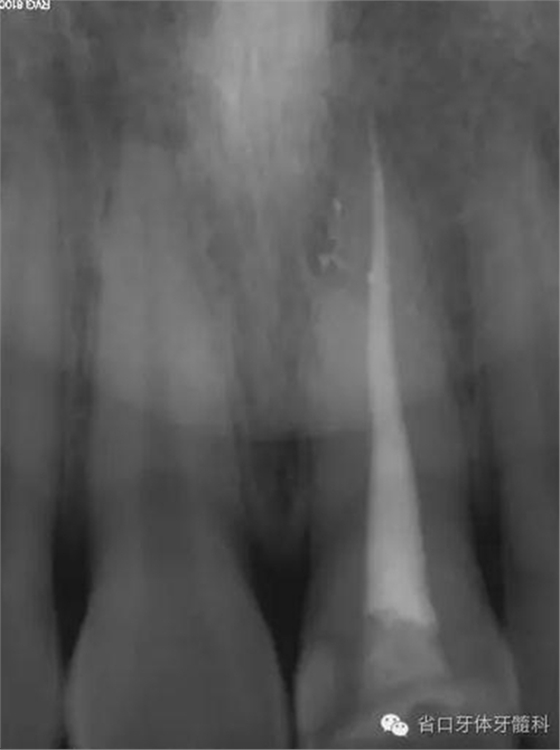

根充后X線片

0.9%生理鹽水沖洗,吸潮紙尖干燥,連續(xù)波熱牙膠充填,拍片示21恰填。

術后x線片